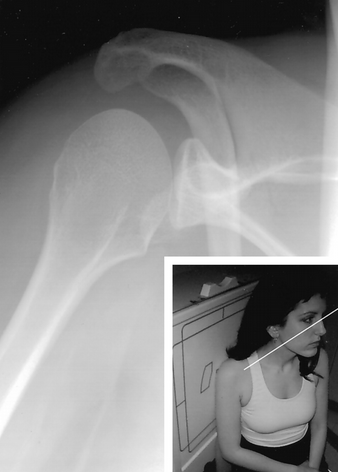

How do you do a Garth View

what are you looking for?

Apical oblique

patient is seated with the arm at the side;

Looking for anterior bankart